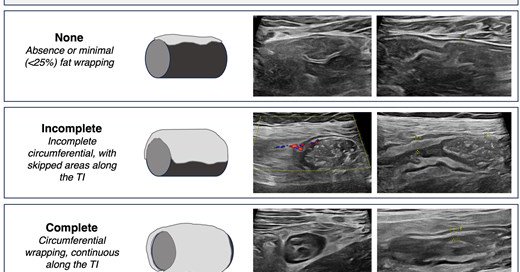

Excited to share our work spearheaded by @joelle_stpierre - Reliability and Validity of Mesenteric Fat Assessment by IUS in Pediatric CD Using the Chicago Mesenteric Fat Index https://t.co/CtKMnZv0Su Adult study coming soon! @DrMikeDolinger @mattsmyth_gi @KrugCleveland @IBDMD

AbstractBackground. Intestinal ultrasound (IUS) provides a noninvasive means of assessing Crohn’s disease (CD), including visualization of mesenteric fat (